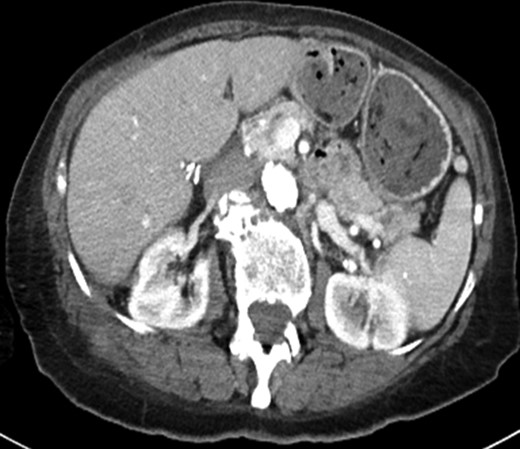

(a) Axial image of the CT of the abdomen with IV contrast, demonstrating a complex partially cystic, partially solid enhancing mass abutting the right hepatic lobe and right kidney and extending into the abdominal wall. (b) Axial T2-weighted sequence of the abdomen (axial T2 Single Shot Fast Spin Echo) showing the cystic component of the mass involving the right retroperitoneal space. (c) Axial T1-weighted fat saturation post-contrast sequence of the abdomen (axial T1 Liver Acquisition with Volume Acquisition after the intravenous administration of gadolinium) demonstrating enhancement of the solid component of the mass extending to the right flank musculature. (d) PET/CT showing increased FDG activity at the solid component identified on CT and MRI within the right flank musculature.

Positron emission tomography-computerized tomography revealed hypermetabolism (Fig. 1d) with maximum Standard Uptake Value of 13.4 g/ml. No overt metastatic spread was identified. The patient was referred for STS multi-disciplinary evaluation including discussion at Sarcoma Tumor Board. Careful review by a musculoskeletal radiologist highlighted the presence of cholecystectomy clips, fascial plane violation and round foci of calcium density (Fig. 3a and b). This raised suspicion for possible retained gallstones, especially since the violation of fascial planes was atypical for STS.